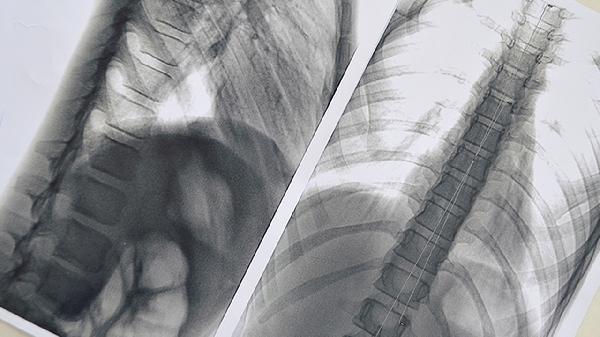

做完支气管镜后肺部隐隐作痛可能是检查过程中的黏膜刺激或轻微损伤引起的,通常1-3天可自行缓解。若疼痛持续加重或伴随发热、咯血等症状,需警惕气胸、感染等并发症。

少数情况下,疼痛可能与并发症相关。检查后若出现持续锐痛且伴随呼吸困难,需考虑气胸可能,多因肺组织被器械划伤导致气体漏入胸腔。感染性疼痛通常起病较慢,但会逐渐加重,可能伴有黄痰或发热,与消毒不彻底或术后护理不当有关。极少数患者因基础疾病如肺气肿,检查后可能出现肺泡破裂出血。